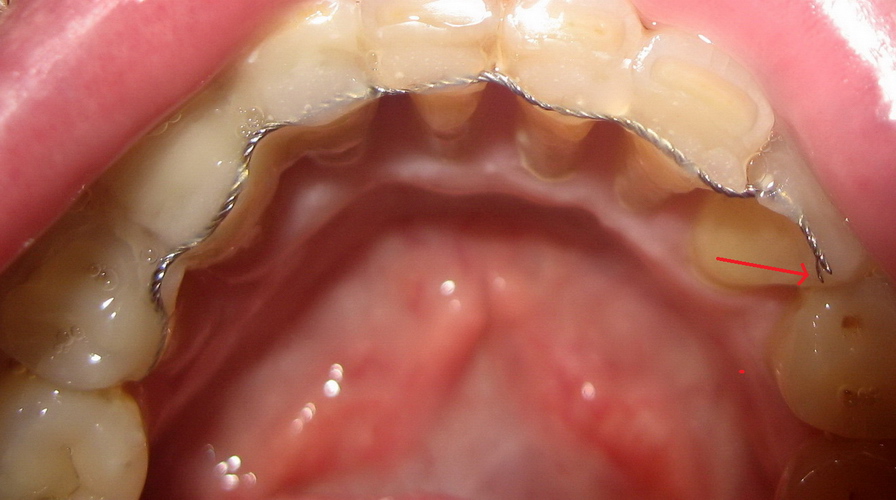

Blue Giant Le Géant Bleu | Vous voulez des dents blanches ? On va vous les limer. Mais comment peut-on en arriver là ? Message édité par Blue Giant le 21-12-2021 à 04:05:01 --------------- Certains font payer les pigeons... d'autres élèvent des pingouins ! - Mon Feed-back ! |